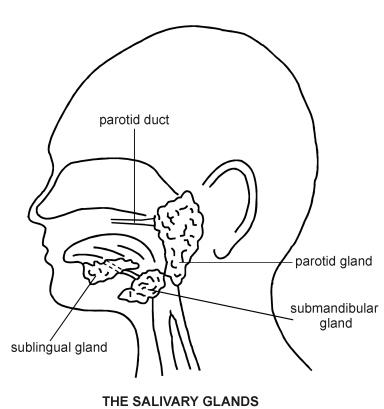

Salivary gland anatomy and physiology

Approximately 1-1.5 L/day of saliva are produced by three pairs of major salivary glands:

The parotid glands lie below the external auditory meatus, between the vertical ramus of the mandible and the mastoid process. The parotid duct crosses the masseter and opens via a small papilla on the buccal membrane opposite the crown of the second upper molar. The parotid gland has an intimate relationship with the facial nerve, which subdivides into its branches as it passes through the parotid.

The submandibular glands are walnut-sized paired structures, lying beneath and in front of the angle of the jaw, wrapping around the posterior edge of the mylohyoid muscle. Their ducts emerge to the floor of the mouth just lateral to the frenulum of the tongue.

The sublingual glands lie below the tongue and open through several ducts to the floor of the mouth.

There are also a large number (600-1,000) of minor salivary glands widely distributed throughout the oral mucosa, palate, uvula, floor of the mouth, posterior tongue, retromolar and peritonsillar area, pharynx, larynx and paranasal sinuses.